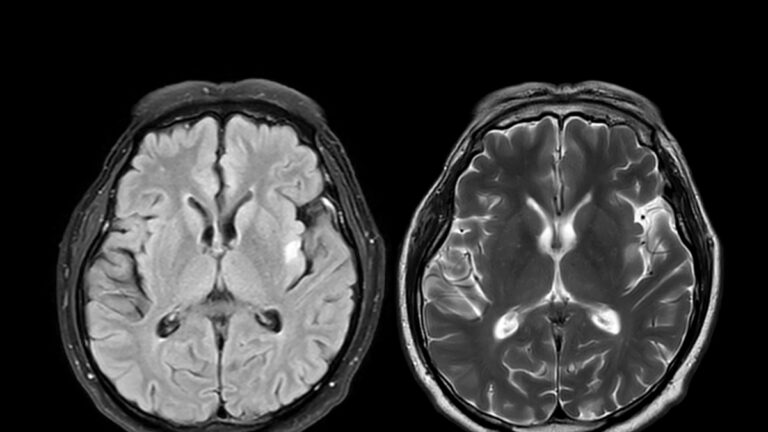

La maladie de Parkinson est liée à la dégénérescence des neurones dopaminergiques, des cellules nerveuses présentes dans une zone du cerveau appelée « substance noire » et qui jouent un rôle très important dans la régulation des mouvements, via un neurotransmetteur particulier, la dopamine. Dans la plupart des cas, les causes sont inconnues, mais on pense que des facteurs environnementaux et génétiques, mais pas seulement, sont impliqués.

«Lorsque le traitement médicamenteux ne suffit plus, d’autres approches entrent en jeu. En particulier, la stimulation cérébrale profonde (DBS) qui représente aujourd’hui une solution consolidée pour certains patients aux stades avancés – rapporte Pezzoli -. Grâce à des électrodes implantées dans des zones spécifiques du cerveau, nous pouvons moduler les circuits modifiés et améliorer considérablement les symptômes. »

A côté de cette technique, d’autres technologies apparaissent, comme les ultrasons focalisés guidés par résonance magnétique, mais pour l’instant les indications sont encore limitées.